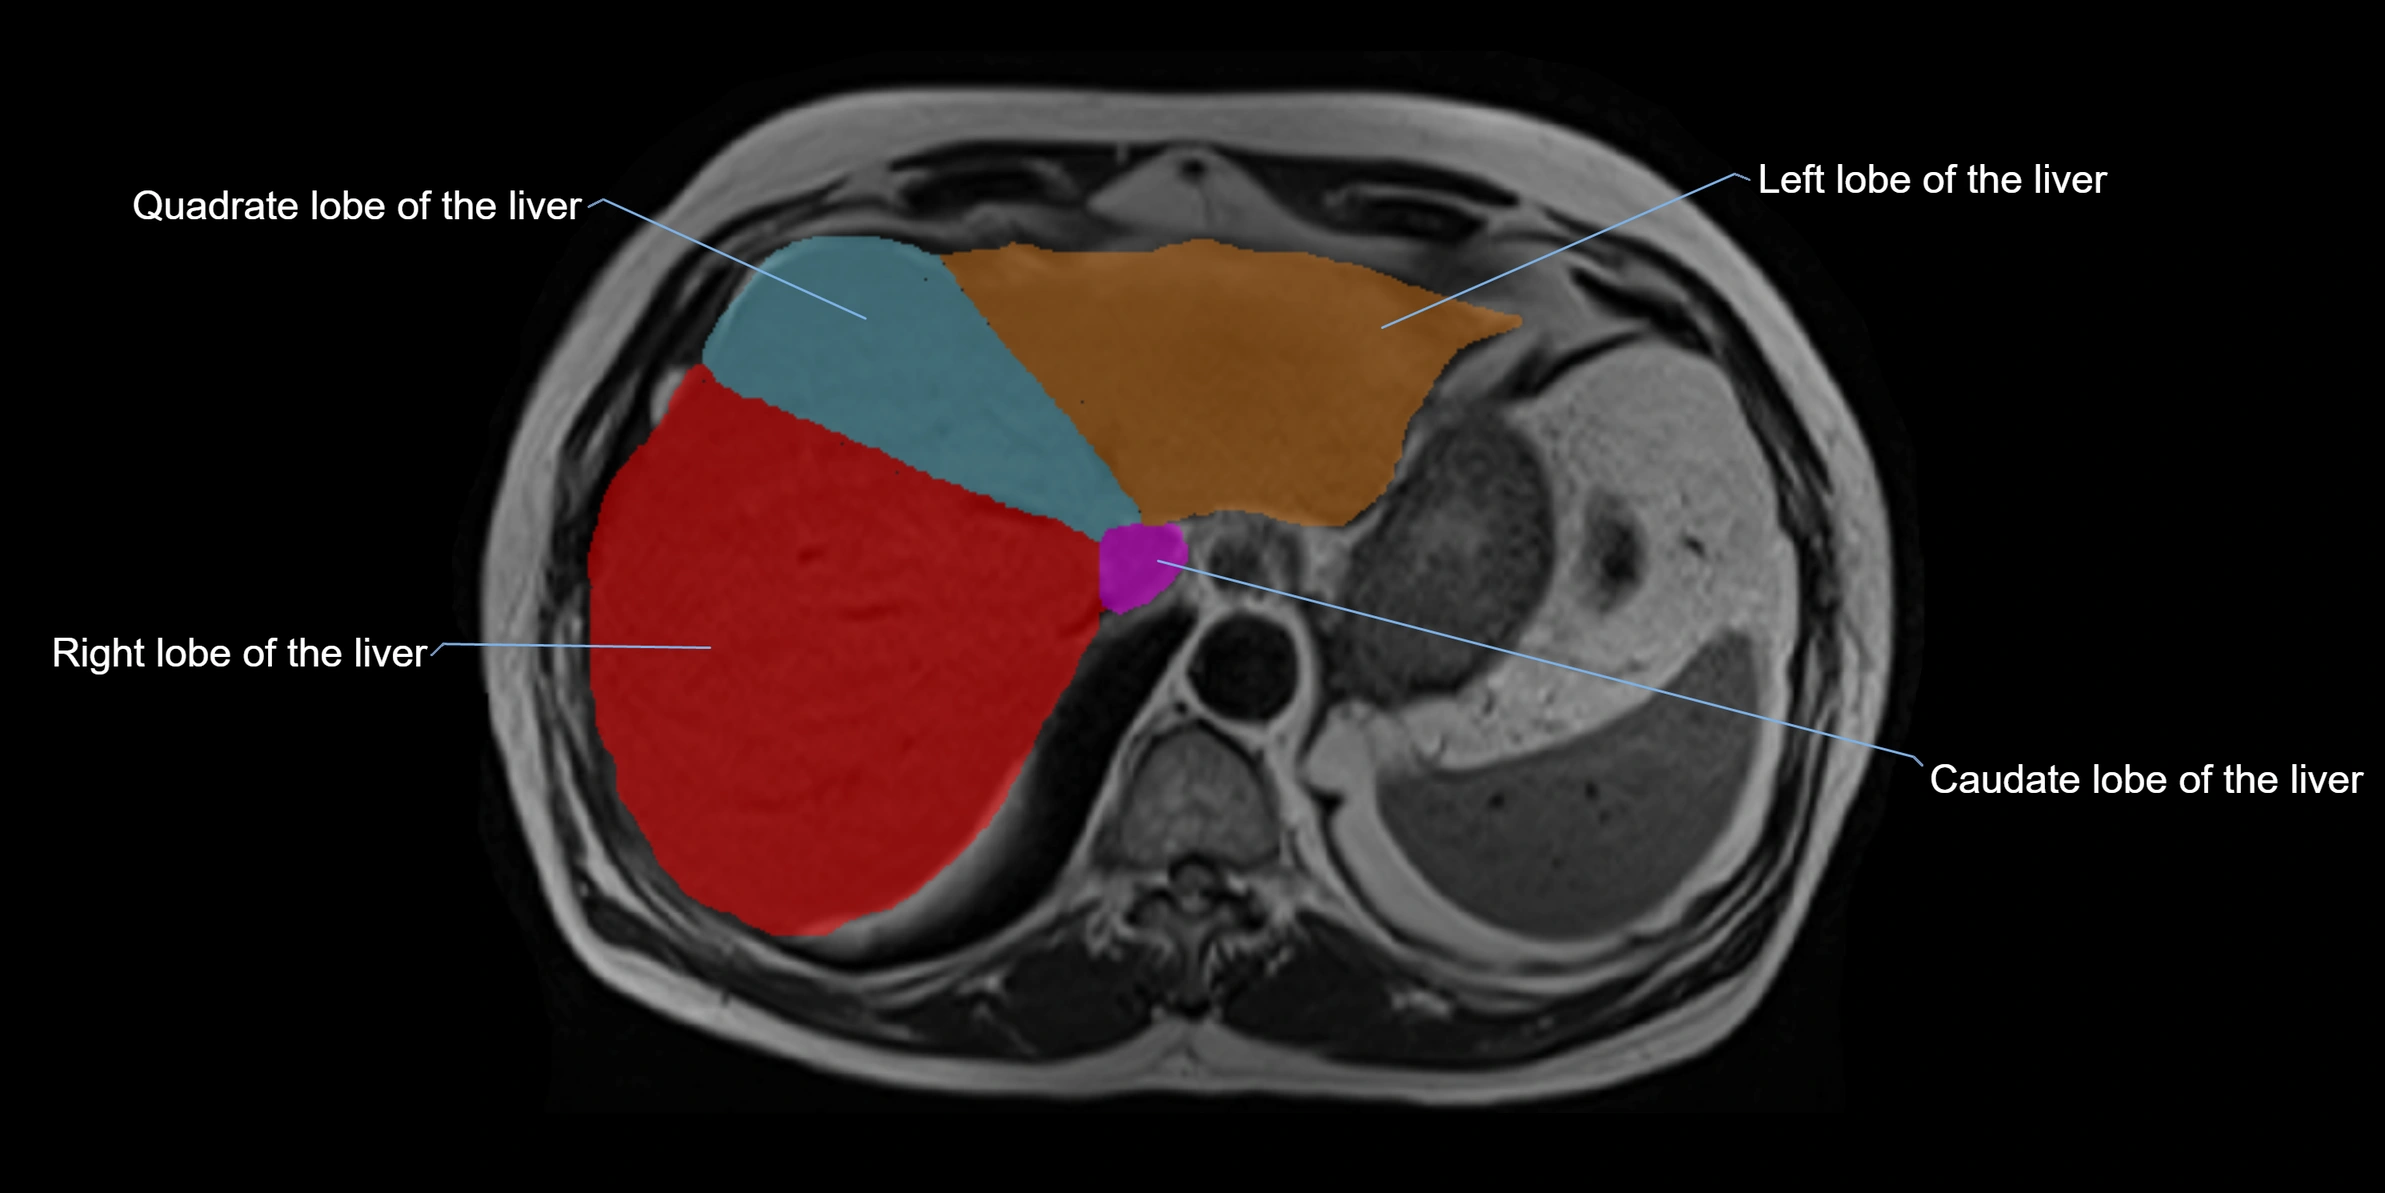

The caudate lobe of the liver is a distinct anatomical subdivision of the liver, designated as segment I in Couinaud’s classification. It lies on the posterior surface of the liver, between the fissure for the ligamentum venosum (left boundary) and the groove for the inferior vena cava (IVC) (right boundary). Superiorly, it is related to the posterior liver surface, and inferiorly it is separated from the left lobe by the porta hepatis.

The caudate lobe is unique because it receives dual portal venous and arterial inflow from both the right and left portal veins and hepatic arteries. It also has independent venous drainage directly into the IVC via multiple small hepatic veins, unlike other lobes that drain through the three main hepatic veins.

This anatomical autonomy makes the caudate lobe especially significant in liver surgery, transplantation, and hepatic venous outflow obstruction syndromes (e.g., Budd–Chiari syndrome). Enlargement of the caudate lobe is a characteristic imaging feature in chronic liver disease and cirrhosis.

MRI image

image